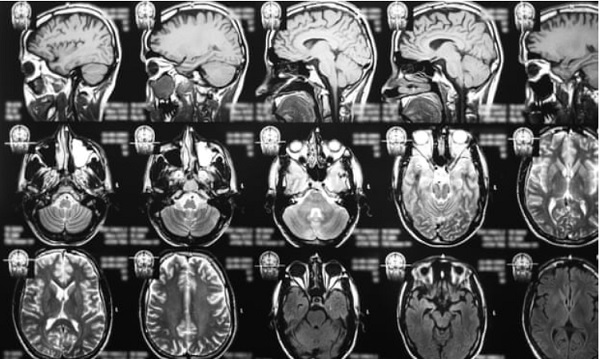

Ảnh chụp cộng hưởng từ não.